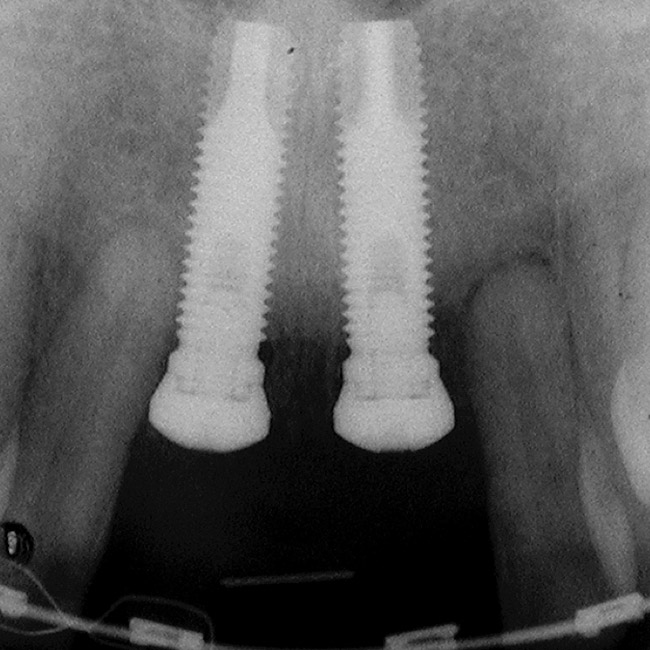

Figure 5  A patient presented needing both centrals extracted. Note the excellent papillary height and free gingival margin location.

Figure 5

Figure 6  Excellent interproximal crestal bone level between the centrals before extraction.

Figure 6

Figure 7  Because the interproximal crestal bone was maintained and the soft tissue supported at the time of tooth removal, an excellent interimplant papilla exists.

Figure 7

Figure 8  Maintenance of interproximal crestal bone following final restoration placement.

Figure 8

Figure 9  The final restorations exhibit a minimal 1-mm to 1.5-mm change in papilla height when compared with the pre-extraction height.

Figure 9